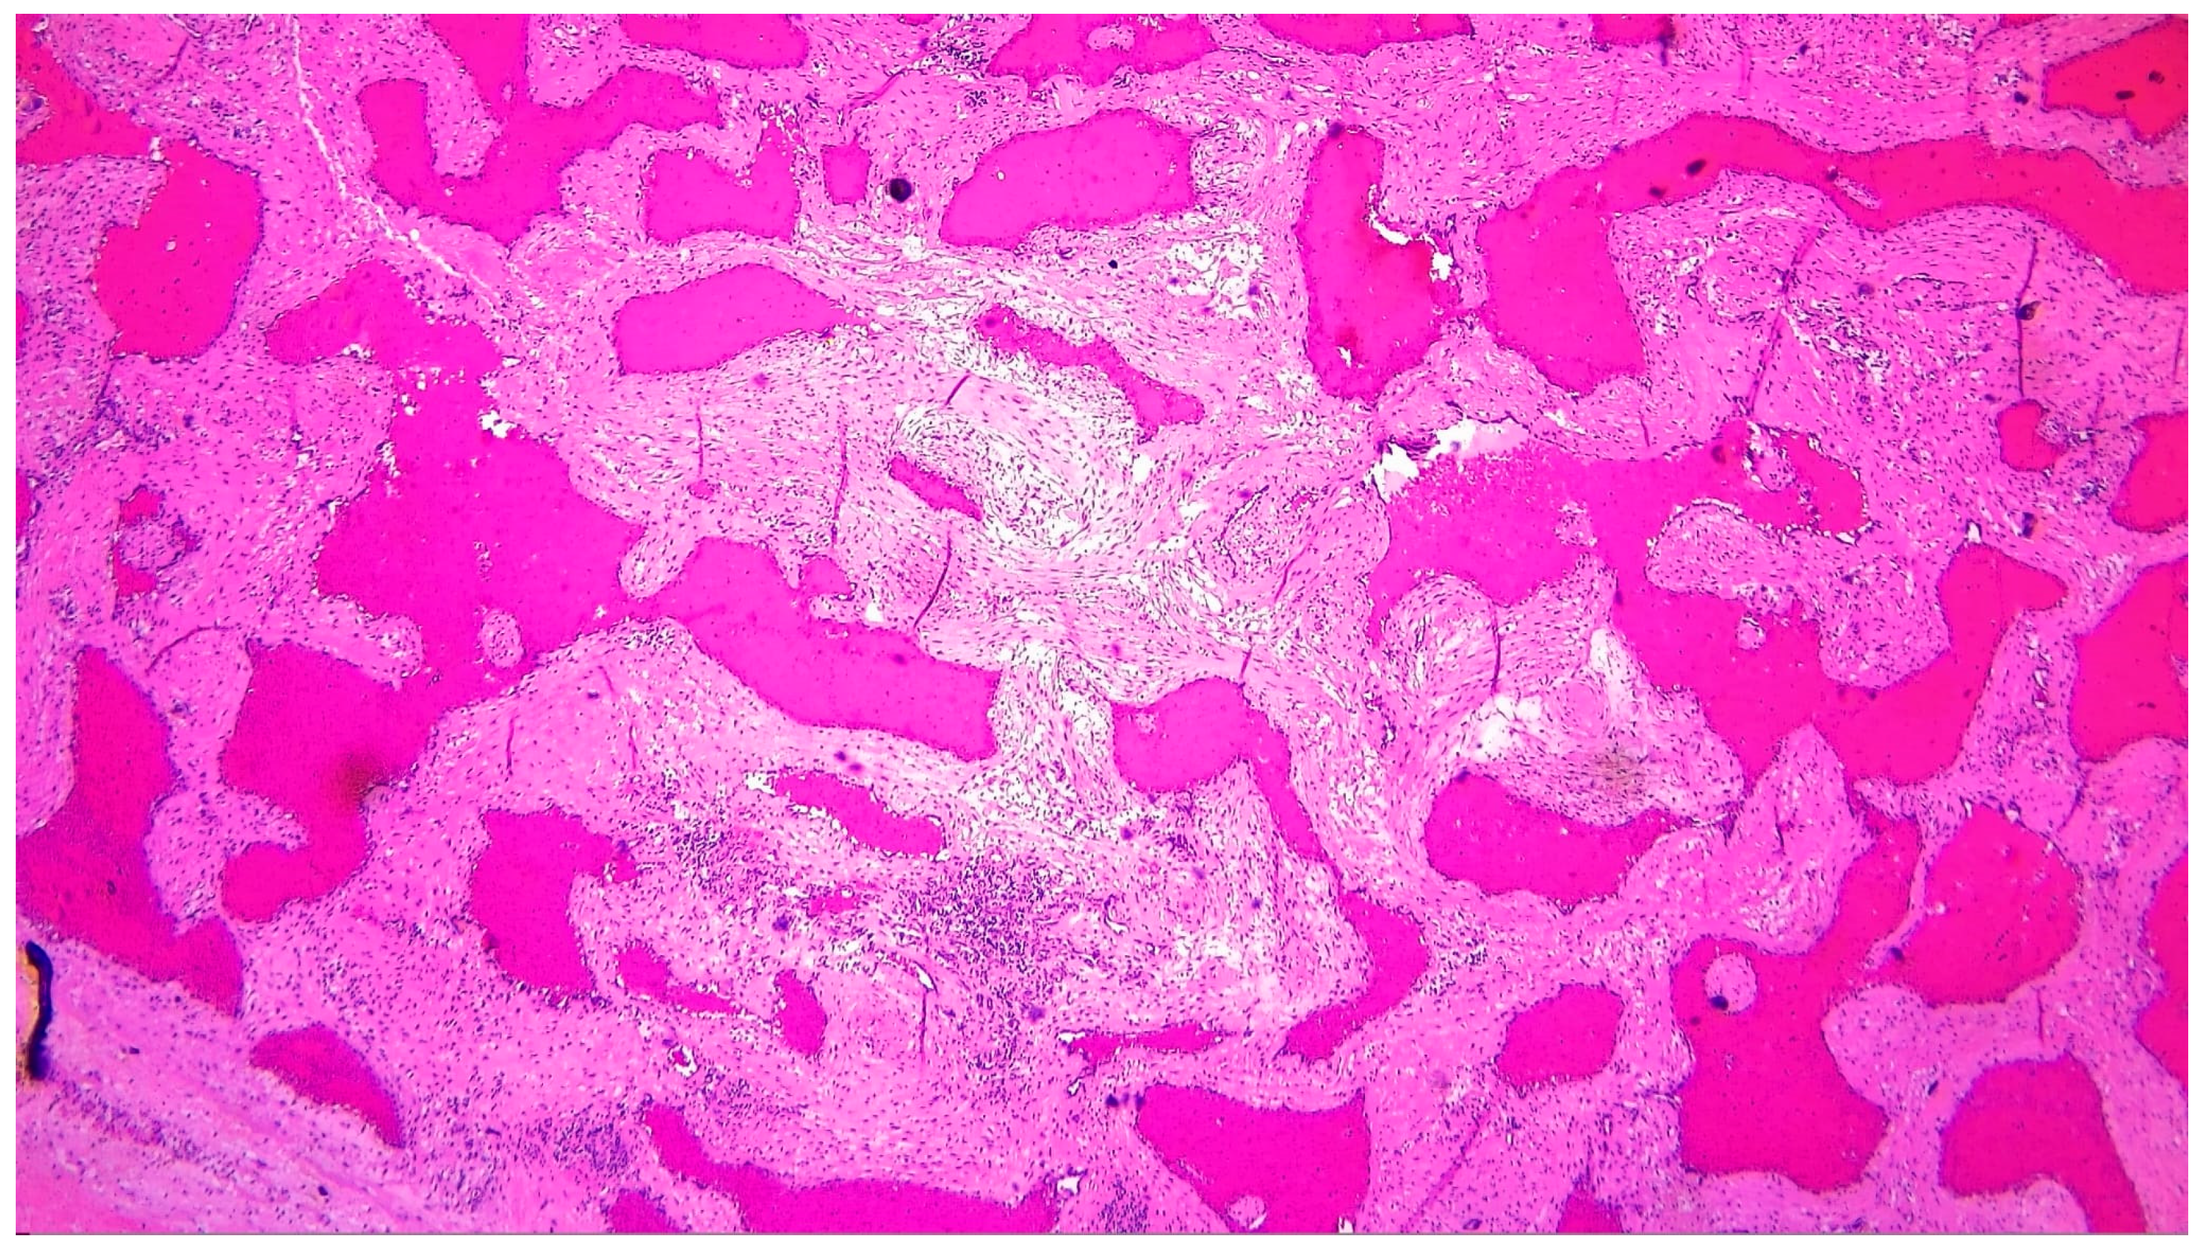

| Histopathology | Gross specimen: nodular, spongy mass (5.5 × 5 × 3 cm). Microscopy: cavernous hemangioma characterized by dilated vascular channels lined by flattened endothelial cells, with fibrous and focal myxoid stroma. |